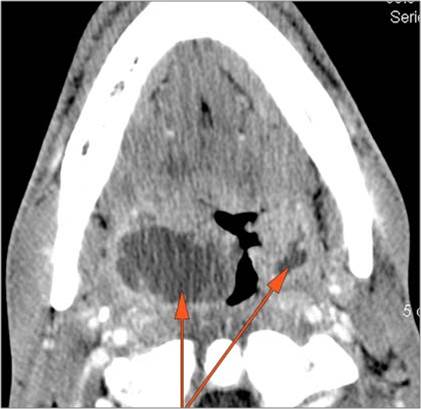

Oral Cavity, Floor of the Mouth, Maxilla and Mandible

There is edema/abscess within or surrounding the buccal space, masticator space, floor of the mouth, submandibular space or the adjacent superficial fascia or subcutaneous fat and skin.